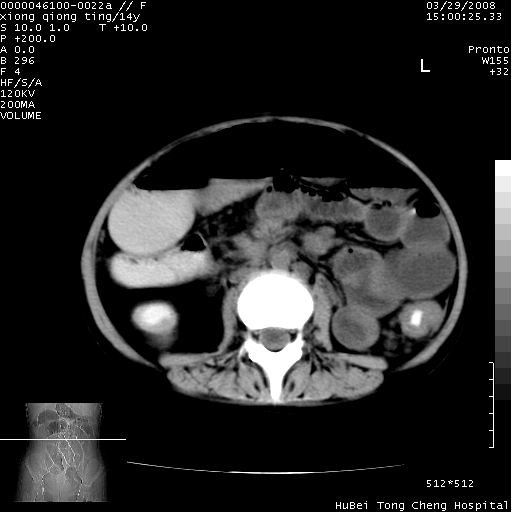

中下腹及盆腔ct轴位平扫+增强扫描(层厚10mm,螺距1.0,重建间隔10mm),图像如下:

(注:患儿检查当日上午9时口服胃肠道对比剂,下午3时许行ct扫描检查,未行对比剂直肠保留灌肠,检查当日患儿腹泻)

中下腹及盆腔ct轴位扫描(ps+ce)提示:腹部肠管明显充气扩张,并见数个不同宽度之气液平面;疑不全性肠梗阻或肠郁张。临床会诊考虑为患儿腹泻,肠郁张所致;后来未经特殊处理,患儿大便恢复正常,亦无腹胀。

临床出院诊断:1)结核性腹膜炎。2)腹膜后淋巴结结核。3)脂肪肝。